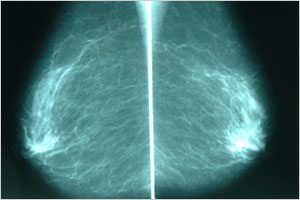

マンモグラフィ専用装置

赤枠内の白い部分が乳がん腫瘤

乳がんに伴う石灰化